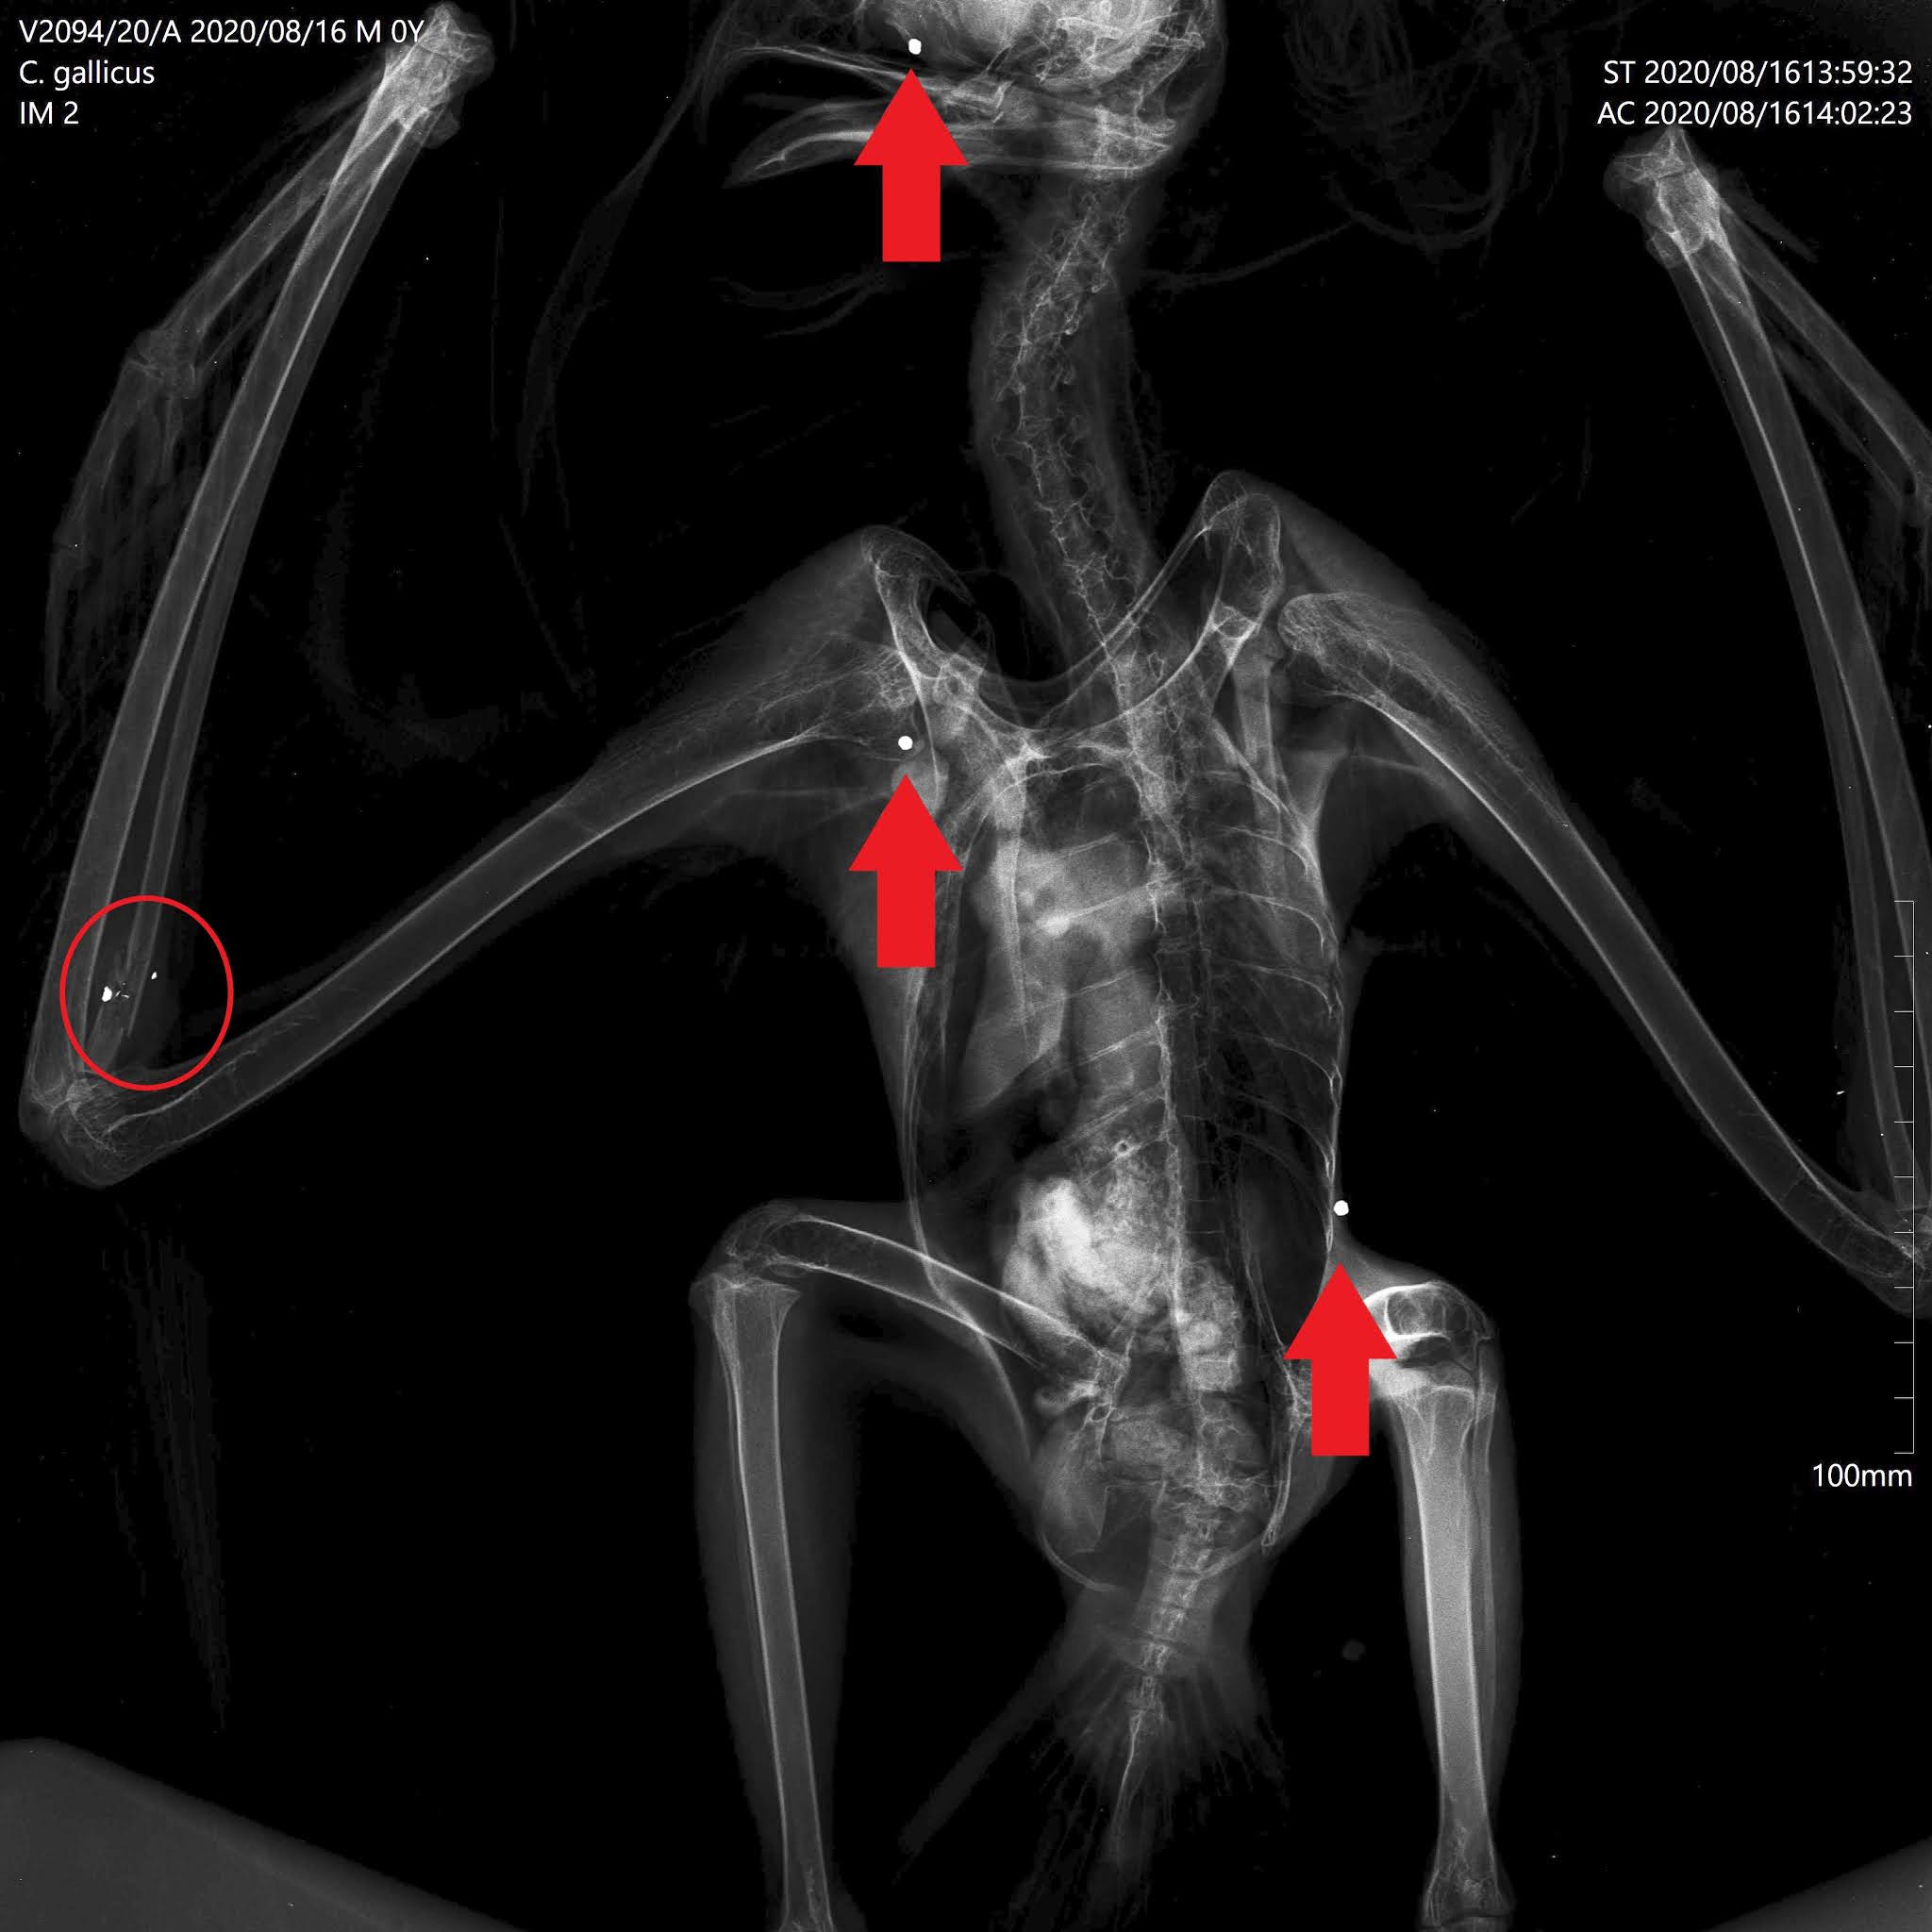

Durante o exame físico foi detectada uma fractura proximal no rádio direito. Suspeitando-se de tiro, a equipa veterinária decidiu realizar um exame radiológico, onde se confirmaram estas suspeitas. Foram identificados três projécteis de caçadeira: na cabeça, ombro direito e costado esquerdo, e restos de um quarto projéctil no foco da fratura.